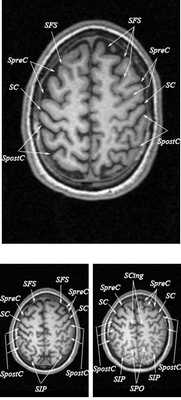

Знание анатомии мозга очень важно для правильной локализации патологических процессов. Ещё более важно оно для изучения самого мозга с помощью современных «функциональных» методов, таких как функциональная магнитно-резонансная томография (fMRI), и позитронно-эмиссионная томография. С анатомией мозга мы знакомимся ещё со студенческой скамьи и существует множество анатомических атласов, в том числе и поперечных сечений. Казалось бы, зачем ещё один? На самом деле, сравнение МРТ срезов с анатомическими приводит к множеству ошибок. Это связано как со специфическими особенностями получения МРТ изображений, так и с тем, что строение мозга очень индивидуально.

Представленная страница сайта основана на специальном изучении МРТ головного мозга здоровых лиц. Для этого изображения получали с минимальной величиной воксела (1 мм в каждом измерении), что исключало наслоения борозд. Каждая из структур прослеживалась в трёх реконструированных плоскостях путём её выделения с помощью компьютерной программы. Мы рассматривали различные анатомические варианты, что обсуждается в работе. В результате, учитывая вариабельность строения мозга, подобран условно «стандартный» мозг. Поскольку на сайте нереально представить 128 срезов в каждой из основных плоскостей, мы ограничились только каждым пятым срезом. Основные срезы в поперечной плоскости даны без наклона назад (угол 0º). Под ними для представления о изменении соотношения анатомических структур демонстрируются срезы, выполненные на тех же уровнях, но с наклонами назад -15º и -30º.

Список сокращений

Борозды

Междолевые и срединные

SC - центральная борозда

FS - Сильвиева щель (латеральная борозда)

SCasc - восходящая ветвь поясной борозды

SCing - поясная борозда

SpreC - предцентральная борозда

SFS - верхняя лобная борозда

SpostC - постцентральная борозда

SIP - внутритеменная борозда

SPO - теменно-затылочная борозда